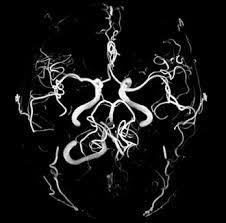

MRI uses a powerful magnetic field, radio frequency pulses and a computer to produce detailed pictures of organs, soft tissues, bone and virtually all other internal body structures. The images can then be examined on a computer monitor, transmitted electronically, printed or copied to a CD. MRI does not use ionizing radiation (x-rays).

Detailed MR images allow physicians to evaluate various parts of the body and determine the presence of certain diseases. - How should I prepare for the procedure?